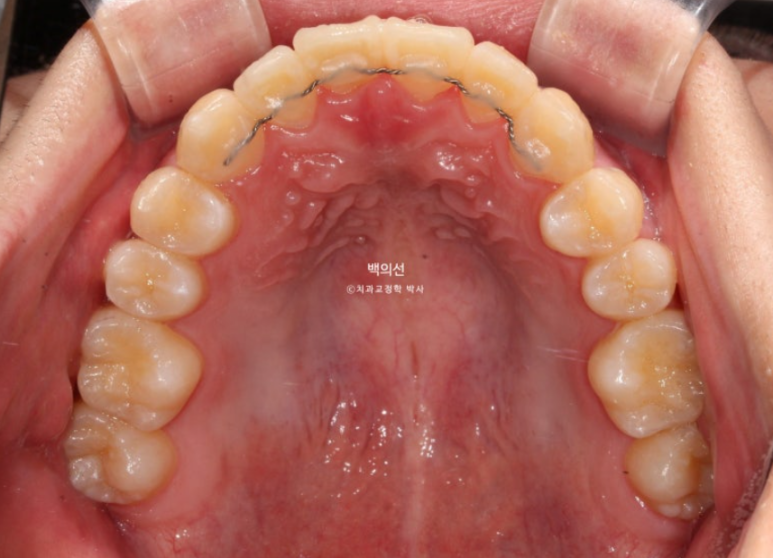

25.07

지금도 충분히 좋지만 추가장치 제작에 들어갔고 25년 2월부터 25년 7월까지 추가장치를 다 낀 후 치료를 마무리 했습니다.

마찬가지로 14개 추가장치를 모두 챙겨가 해외에서 바꿔끼면서 치료를 진행했습니다.

치료 마무리까지 총 내원 횟수는 약 5회 입니다.